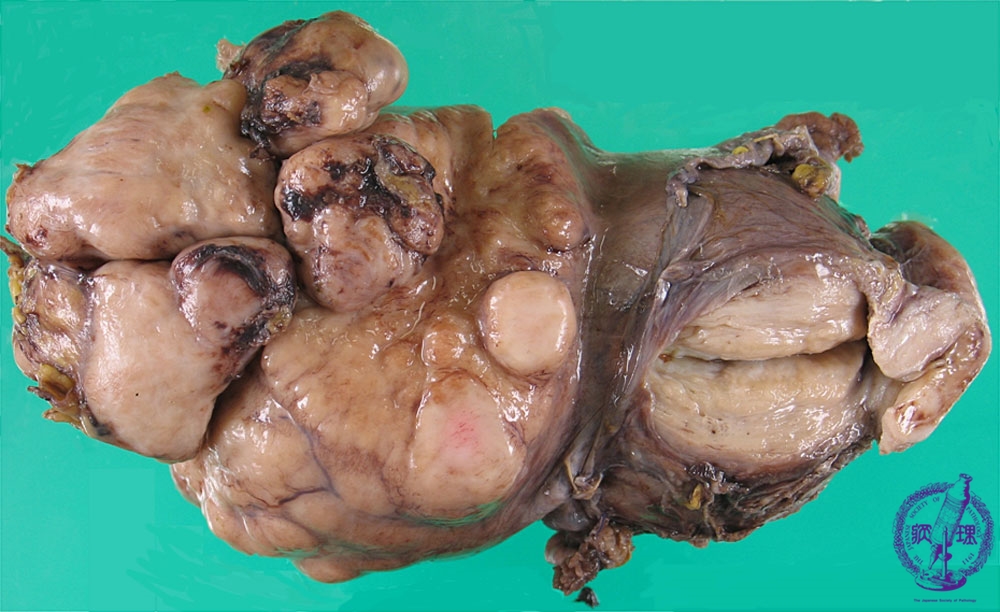

- ★(3)leiomyosarcoma

Macroscopic appearance: A milky white colored and solid tumor (yellow dotted line) with partial hemorrhage and necrosis (yellow arrow).